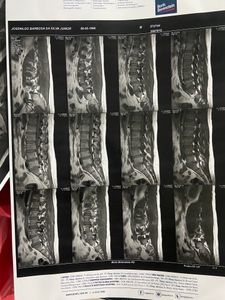

O jovem Júnior sofreu um acidente é pai de 2 filhos e precisa de uma cirurgia na lombar urgente o mesmos e encontra com 3 hérnias não lombar, dificultando realizar tarefas simples do dia a dia, e trabalhar, conto com a ajuda e orações de vocês, para que possamos realizar essa cirurgia com urgência .